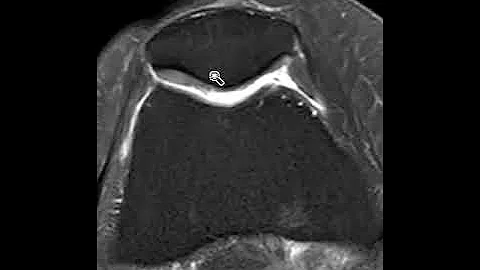

Chondromalacia Patellae - The 4 Stages And Their Treatment Explained

In this video Prof. Dr. Bellemans explains what can be done about chondromalacia patellae, and how the treatment is influenced ...